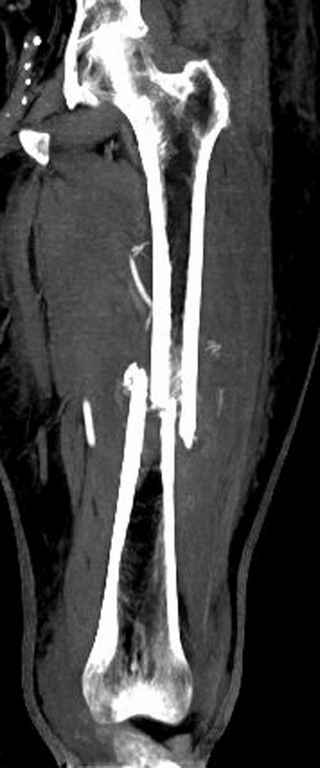

Со слов, больная ничем не болела, только последние 3 месяцев чувствовала боли в бедренной области. КТ брюшной полости подтвердил увеличенную правую почку. (5-6)

Для предупреждения кровотечения во время рассверливания, за день до операции провели эмболизацию сосудов питающий метастаз. http://radiology.rsnajnls.org/cgi/reprint/150/3/673.pdf (7-11, 12-15-16)

С минимальным рассверливанием и ретроградным методом провели остеосинтез бедра 12 мм гвоздем. (17-20)

Кровопотеря во время операции меньше 100 мл.